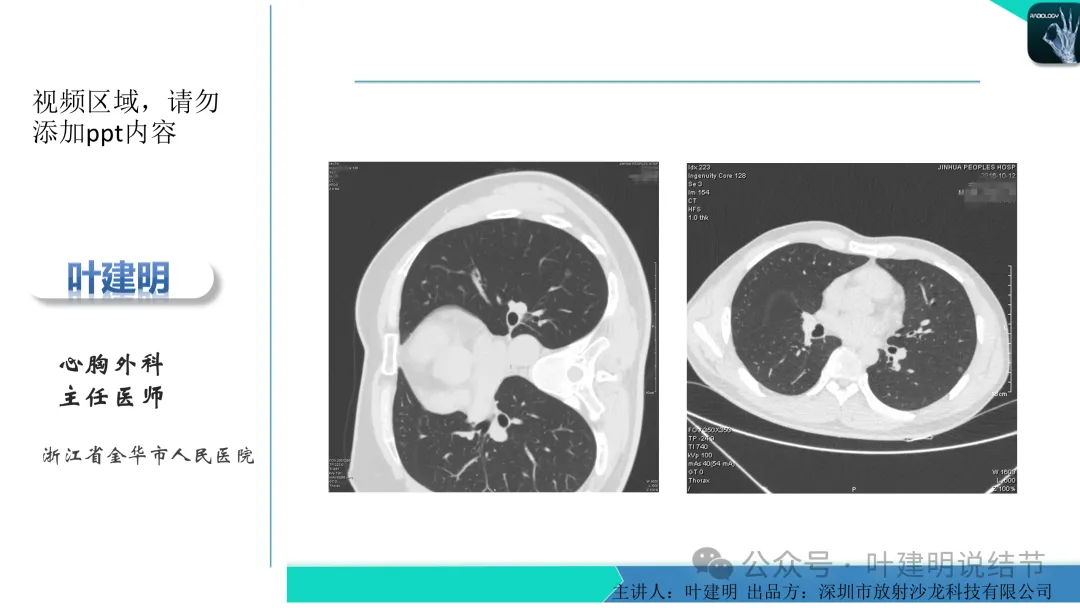

当地说考虑微浸润性腺癌的左下主病灶影像连续层面展示:

病灶出现,显模糊。

上图层面轮廓较清,但密度很淡,似见血管走行,但靠左前方的似条状磨玻璃密度与血管连着的到底是血管分支还是结节的一部分,其实并不确切。如果其实是血管分支,那病灶与它之间就不是空泡。

病灶在此层整体边缘显糊,灶内有空泡似的,瘤肺边界欠清。

边缘不平,还是灶内多发小空泡?邻近血管与之紧贴,但血管无异常走行。病灶密度很低,显糊。

中间所谓空泡更像是细支气管扩张,内壁非常光滑且圆形。

病灶边缘区淡而模糊。